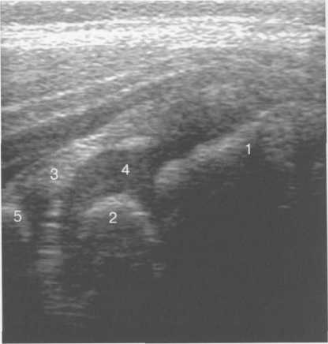

Рис. 19.85. Боковой доступ, продольное сканирование тазобедренного сустава (2 года).

1 — шейка бедренной кости; 2 — ядро оссификации головки бедренной кости; 3 — хрящевой лимбус; 4 — хрящевая часть головки бедренной кости; 5 — контур крыши вертлужной впадины.